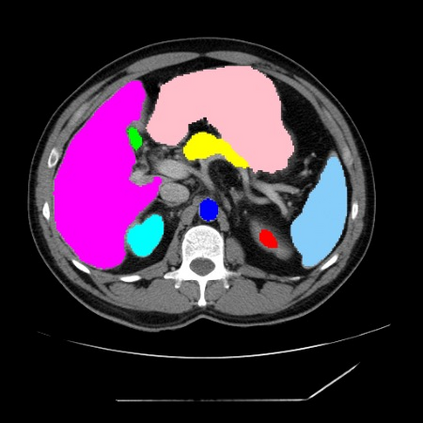

Integrating high-level semantically correlated contents and low-level anatomical features is of central importance in medical image segmentation. Towards this end, recent deep learning-based medical segmentation methods have shown great promise in better modeling such information. However, convolution operators for medical segmentation typically operate on regular grids, which inherently blur the high-frequency regions, i.e., boundary regions. In this work, we propose MORSE, a generic implicit neural rendering framework designed at an anatomical level to assist learning in medical image segmentation. Our method is motivated by the fact that implicit neural representation has been shown to be more effective in fitting complex signals and solving computer graphics problems than discrete grid-based representation. The core of our approach is to formulate medical image segmentation as a rendering problem in an end-to-end manner. Specifically, we continuously align the coarse segmentation prediction with the ambiguous coordinate-based point representations and aggregate these features to adaptively refine the boundary region. To parallelly optimize multi-scale pixel-level features, we leverage the idea from Mixture-of-Expert (MoE) to design and train our MORSE with a stochastic gating mechanism. Our experiments demonstrate that MORSE can work well with different medical segmentation backbones, consistently achieving competitive performance improvements in both 2D and 3D supervised medical segmentation methods. We also theoretically analyze the superiority of MORSE.

翻译:在医学图像分割中,整合高级语义相关的内容和低级解剖特征对于模拟这些信息非常重要。近期基于深度学习的医学分割方法已经显示出很有前景,可以更好地建模这些信息。然而,医学分割的卷积运算符通常在正则化网格上运作,这在本质上模糊了高频区域,即边界区域。我们在这项工作中提出了 MORSE,这是一个设计在解剖学水平上的通用隐式神经渲染框架,用于协助医学图像分割的学习。我们的方法的动机在于隐式神经表示已经被证明比离散化网格表示更有效地拟合复杂信号和解决计算机图形问题。我们方法的核心是将医学图像分割连续地对准粗糙的分割预测和模棱两可的基于坐标的点表示,并聚合这些特征来自适应地精细化边界区域。为了并行地优化多尺度像素级特征,我们借鉴了 Mixture-of-Expert (MoE) 的思想设计和训练我们的MORSE,使用随机门控机制。我们的实验表明MORSE可以很好地与不同的医学分割后骨干结合在一起,始终在2D和3D监督医学分割方法中实现了有竞争力的性能改进。我们还从理论上分析了MORSE的优越性。